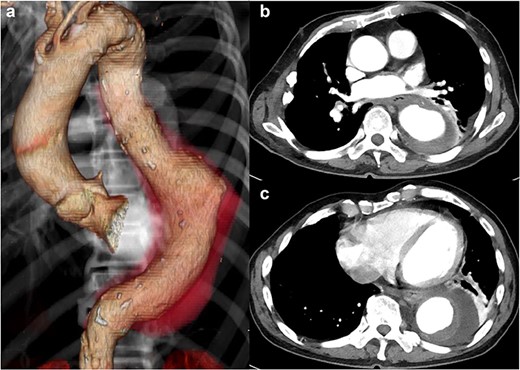

CT 15 months after reconstruction showed regression of the aneurysm, measuring 53 × 53 mm (Fig. 3). He had no further signs of infection.

CT 15 months later shows regression of the aneurysm to 53 mm in diameter.